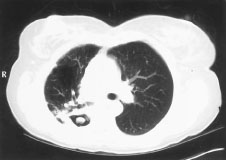

Consists of mycelia, inflammatory cells, fibrin, mucus, and tissue debris. Occurs in pre-existing lung cavities.[Figure caption and citation for the preceding image starts]: Aspergilloma in a pre-existing tuberculous lung cavityFrom the collection of Dr P. Chandrasekar; used with permission [Citation ends].

A single aspergilloma in a single cavity, with no progression and few or no symptoms is termed simple aspergilloma.